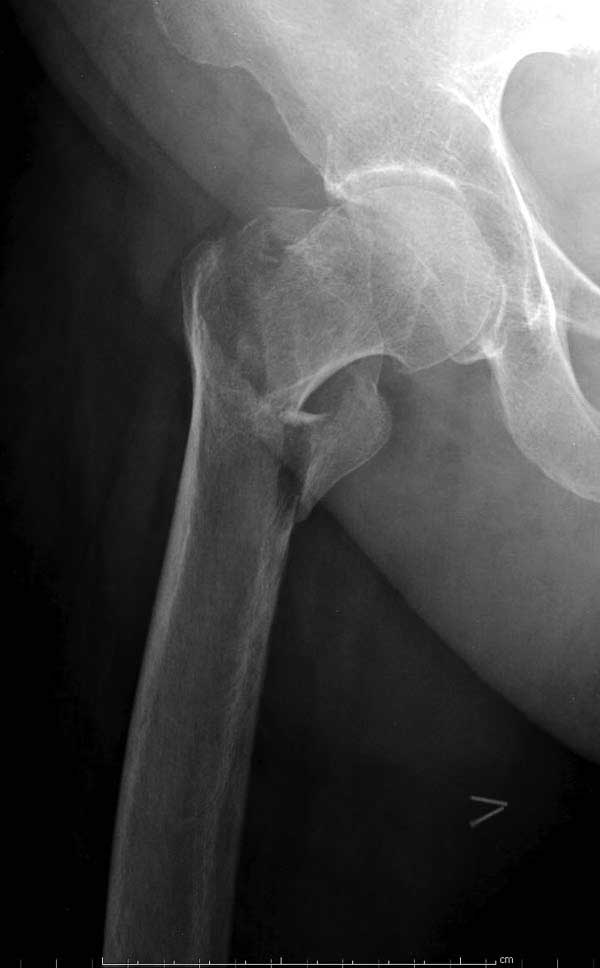

Первые снимки показывают технические погрешности установки DHS. Не была достигнута репозиция, конечность в флексии и шейка в ротации. Сегодня все меньше обращают внимание на параметры для оценки репозиции (S контуры Lowell в обеих проекциях и Garden Alignment Index, в норме 155 и 180 градусов), хотя такие простые тесты помогли бы дорепонировать смещение. Винт находится сзади в головке, что при нагрузке поменяет вектор и вместо компрессии в линии перелома срежет головку-Cut Out!

В заключение: чрезвертельные переломы можно лечить разными методами, включая наружные фиксаторы, но для начала надо определиться, какой это перелом? Стабильные переломы А1 (1-3), А2 (1) можно фиксировать DHS или гвоздем, а нестабильные переломы - гвоздями или современными пластинами для проксимального бедра. Трудным считается Reverse obliquity A3 (1) который из-за скоса перелома лучше удерживает Blade Plate, но современные гвозди неплохо зарекомендовали в лечении таких переломов.